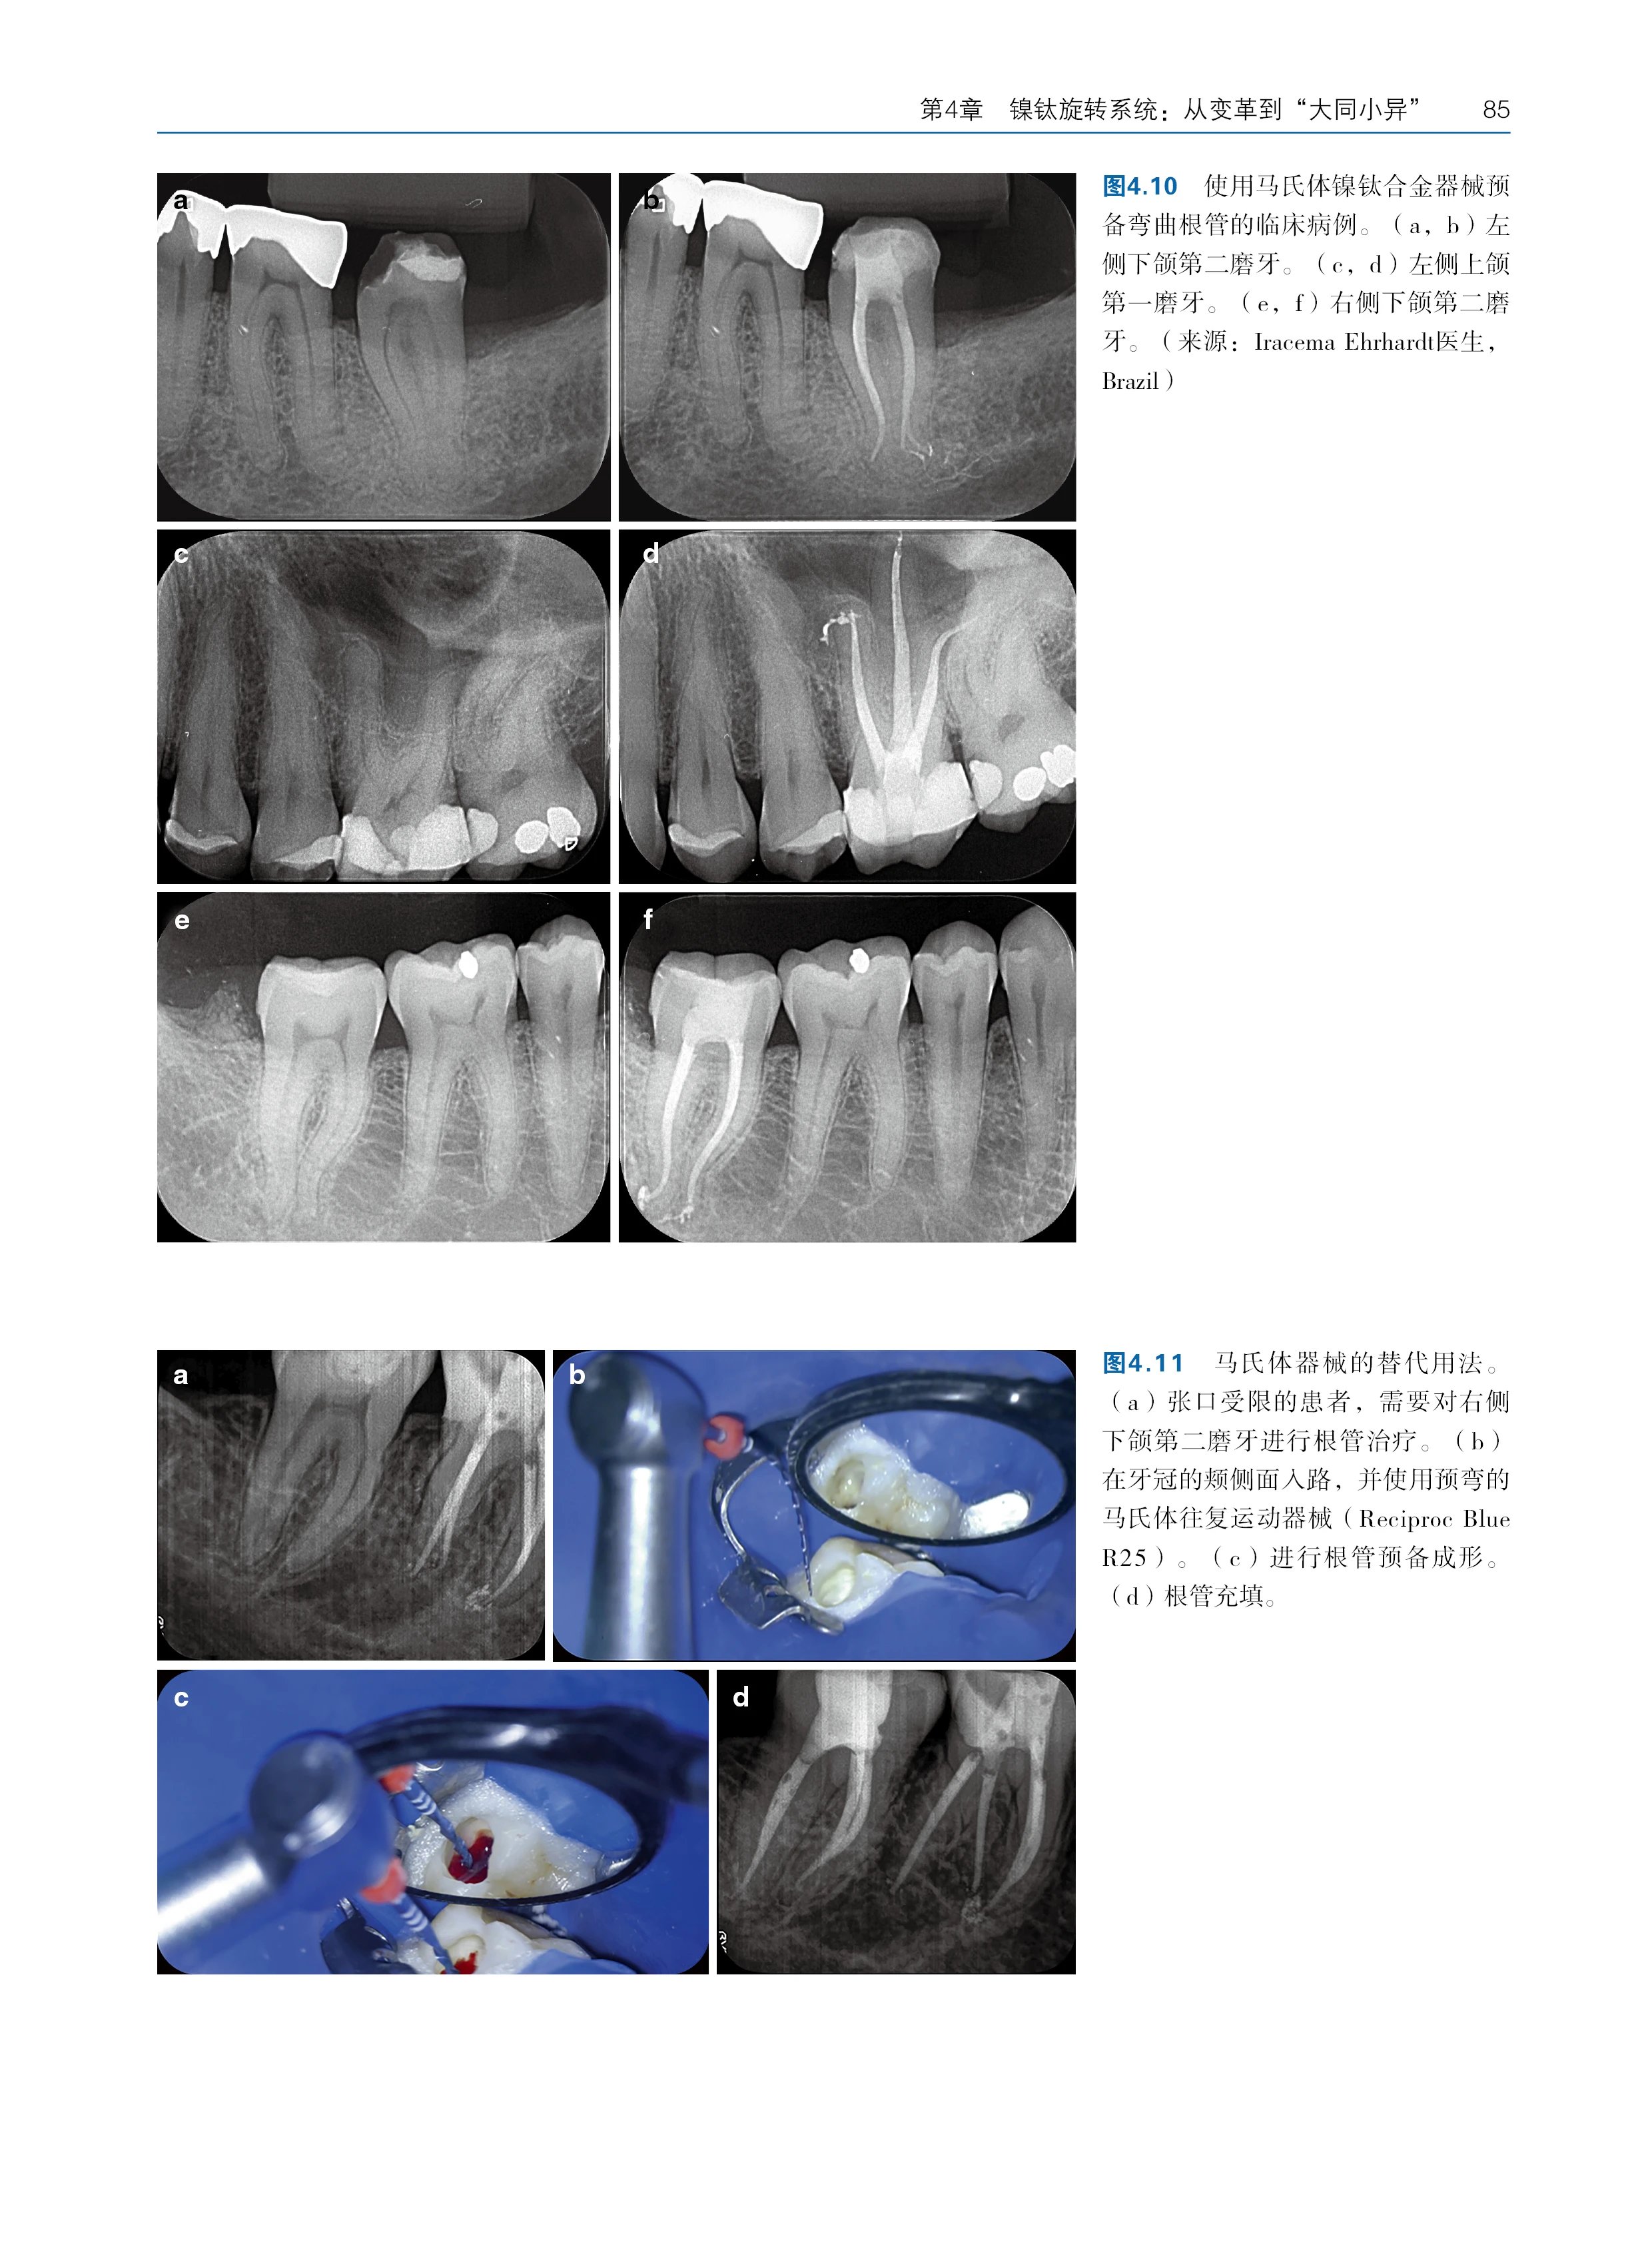

编辑推荐 * 聚焦核心,阐释辩证关系:本书由国际权威专家团队联合编写,系统深入地解析了根管治疗中“清理”和“成形”这对核心概念的辩证统一关系,针对临床医生普遍面临的"过度预备损伤牙体组织"与"残留感染导致治疗失败"的两难困境,指导医生在彻底清除感染与最大限度保存牙体组织之间找到科学精准的平衡点,实现治疗效果与牙齿长期保存的双赢。 * 循证为基,涵盖前沿技术:本书内容基于坚实的循证医学证据,不仅全面比较了传统与现代根管预备技术,还详细分析了各类器械系统在清理效率、成形能力和微创方面的优劣,结合根管形态学分类、感染程度等变量,为临床策略选择提供了个性化治疗方案设计框架。 * 授人以渔,培养临床思维:本书区别于单纯的操作手册,致力于培养医生的科学临床思维。通过大量临床病例和科学数据,系统阐释"为何选择某类器械""何时调整预备策略"等深层逻辑,深入探讨“为何如此操作”,将复杂诊疗过程转化为可量化的科学决策,助力医生快速成长为具备批判性思维的临床专家,是临床医生、教师及学生不可或缺的参考书。 (4)内容简介 面对以镍钛旋转器械为代表的快速成形技术带来的变革,本书对Schilder教授提出的经典“清理和成形”概念进行了更新与重塑。针对传统"清理和成形"概念在新时代的适用性困境,首次提出"为清理而成形"的生物导向治疗哲学,明确指出所有根管成形操作的终极目标应是实现感染控制的生物学效能最大化,而非单纯追求机械预备的形态学指标。 本书不仅系统涵盖了从根管探查、冠部扩大到冲洗、成形的全部技术环节,更以前沿的循证证据为基础,深入探讨了技术革新对每个步骤的影响以及当前消毒技术的局限性。通过整合临床、生物学与材料学的最新科研成果,突破传统操作手册的局限,致力于培养医生的批判性临床思维,帮助其在日新月异的技术浪潮中掌握制订科学、个体化治疗方案的能力,从组织保存率、微生物清除率、长期成功率3个维度建立疗效评估体系。